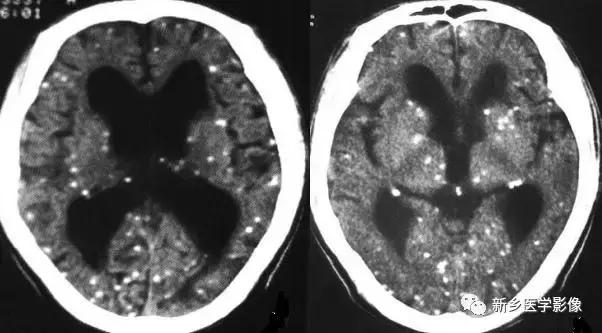

六、甲状旁腺功能低下

临床表现:与低血钾有关,主要表现有癫痫发作、注意力不集中、记忆和定向障碍、白内障、皮肤粗糙。生化检查特点:血清钙降低,血清磷增高。CT表现:钙化多位于基底节区,呈双侧对称性。在丘脑、小脑齿状核、大脑半球皮层下级皮髓质交界区,也可出现两侧较对称,呈斑片状、条形、月牙状或点状钙化。